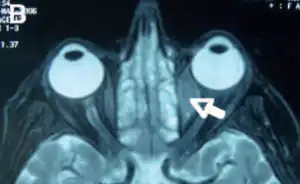

| Infiltrationat the level of the medium straight muscle of the LE which is shown in the axial NMR | |